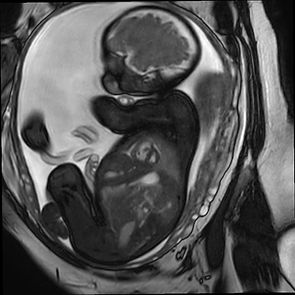

smart-sync is a Doppler ultrasound (DUS) based gating device for MRI. It detects and synchronises the fetal cardiac cycle with the MR system and enables a brand new-kind image quality.

Fetal smart-sync is a Doppler ultrasound (DUS) gating technology that synchronizes the fetal cardiac cycle with the MRI acquisition, enabling clear, motion-free images of the fetal heart.

It provides pin-sharp visualization of intracardiac and extracardiac structures, enhancing diagnostic precision, especially in complex CHD cases where echocardiography alone may be insufficient.

It solves longstanding challenges in fetal cardiology and enables detailed assessment of function, morphology and hemodynamics.

Traditional fetal MRI struggles with motion artifacts from the fetal heartbeat.

smart-sync uses Doppler ultrasound (DUS) gating to detect and synchronize the cardiac cycle automatically. Resulting in first-time crisp fetal heart imaging.